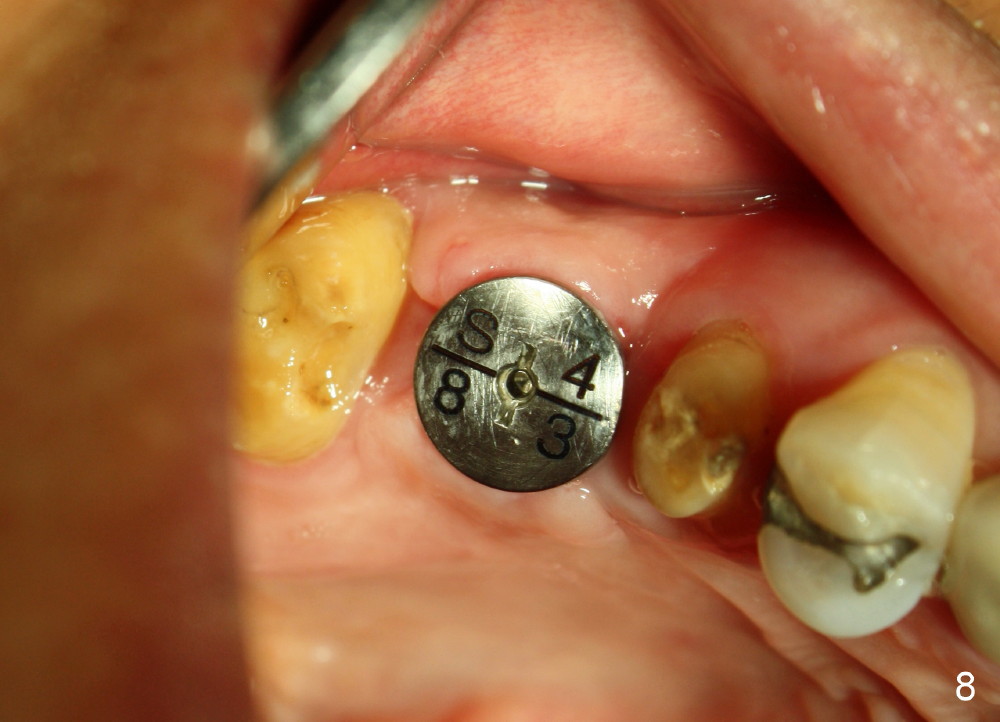

The bone density (Fig.1 white *) at the edentulous area (#3) is lower than that at the dentulous one (black *, 50 year-old man). The buccal plate is also atrophic and concave (Fig.2,3 arrowheads). A series of bone expanders are used to form osteotomy (following 1.6 mm pilot drill) at the depth of 14 mm (Fig.3 E 3.0 mm in diameter). When the last expander (4.3 mm) is removed from the osteotomy, the buccal plate appears to have been moved buccally (Fig.5 arrowheads). A 5.3x14 mm submerged implant (Fig.6 I) is placed with insertion torque >35 Ncm. The buccal plate seems to improve following placement of an 8.2 mm healing abutment and suturing (Fig.7). No bone graft is used. The buccal plate remains normal 12 days postop (Fig.8). It is slightly concave 3 months postop (Fig.9) with minimal bone resorption at the crest (Fig.10 (H: healing abutment),11 (A: cemented abutment). Nine months post cementation (12 months postop), bone resorption at the crest remains minimal (Fig.12) while the buccal plate (Fig.13 *) at #3 remains strong. Bone loss appears not to get worse 22 months post cementation (Fig.14). Soft and hard tissues remain healthy around the implant crown 3 years (Fig.15) and 3.5 years (Fig.16,17) post cementation.